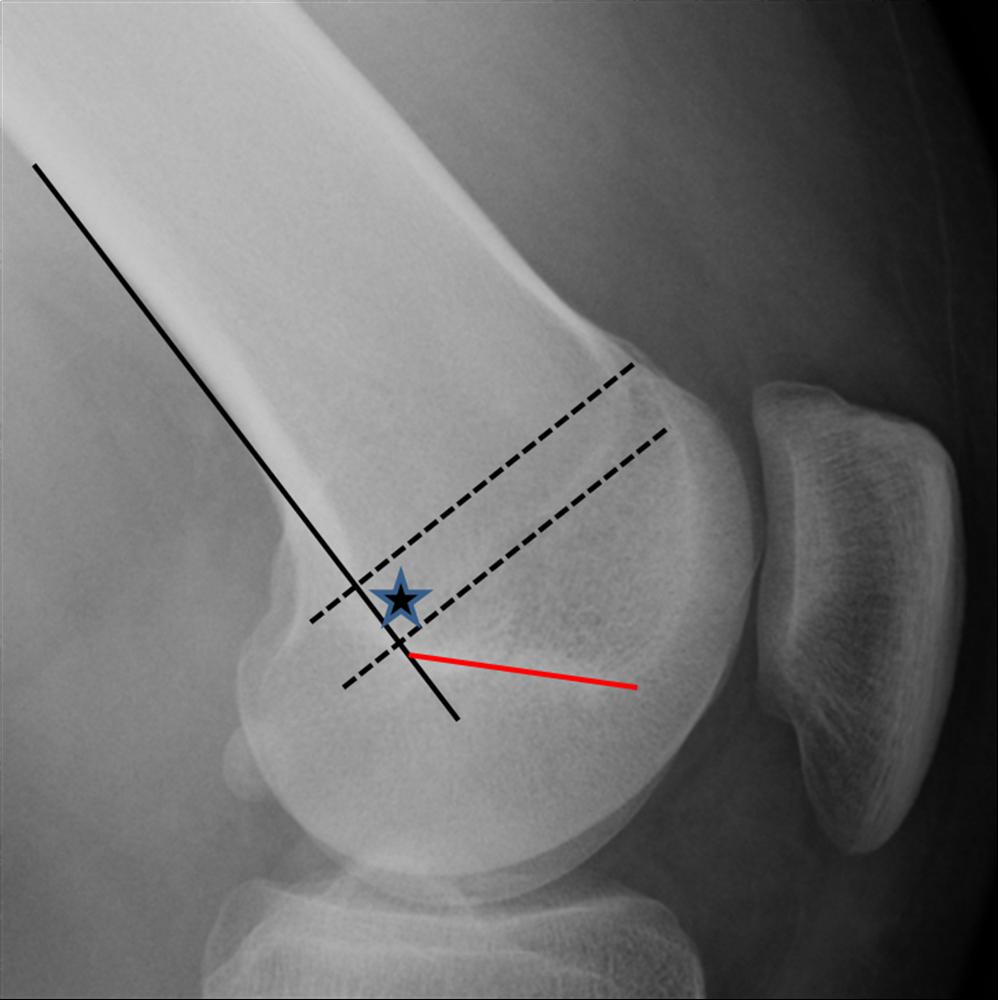

Patellar Instability Knee & Sports Orthobullets Locking Knee Orthobullets Find out the range of motion, q angle, and screw. Learn about the anatomy, function, and stability of the knee joint, including the patellofemoral and tibiofemoral articulations. Learn about meniscus tear, a knee injury caused by meniscal tears, categorized into two types: A mechanical cause of the locked knee can be identified consistently using three key components from the history. Locking Knee Orthobullets.

From orthopaedicprinciples.com